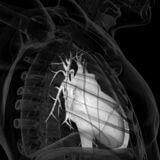

Congenital heart disease management continues to improve at a rapid pace, with recent decades having remarkable advances in transcatheter procedures, minimally invasive surgery, and even prenatal intervention. However, it is crucial to acknowledge the unique challenges encountered in patient care, such as late presentation and the need to minimize fluoroscopy and contrast agents, especially in vulnerable populations like small children and pregnant women. Moreover, staying abreast of emerging techniques and devices is essential. This underscores the necessity for a customized approach in patient management. Interventional pediatric cardiologists and cardiac surgeons must broaden their expertise to effectively address congenital heart diseases in both pediatric and adult patients.

This Research Topic aims to delve into contemporary surgical and non-surgical interventions for treating congenital and structural heart diseases across various age groups. It encompasses a spectrum of catheter-based procedures, practical intervention insights, and minimally invasive surgical methodologies. Furthermore, it will undertake a critical assessment of the merits and demerits of existing technologies utilized for similar therapeutic objectives, providing invaluable insights for enhancing clinical outcomes.